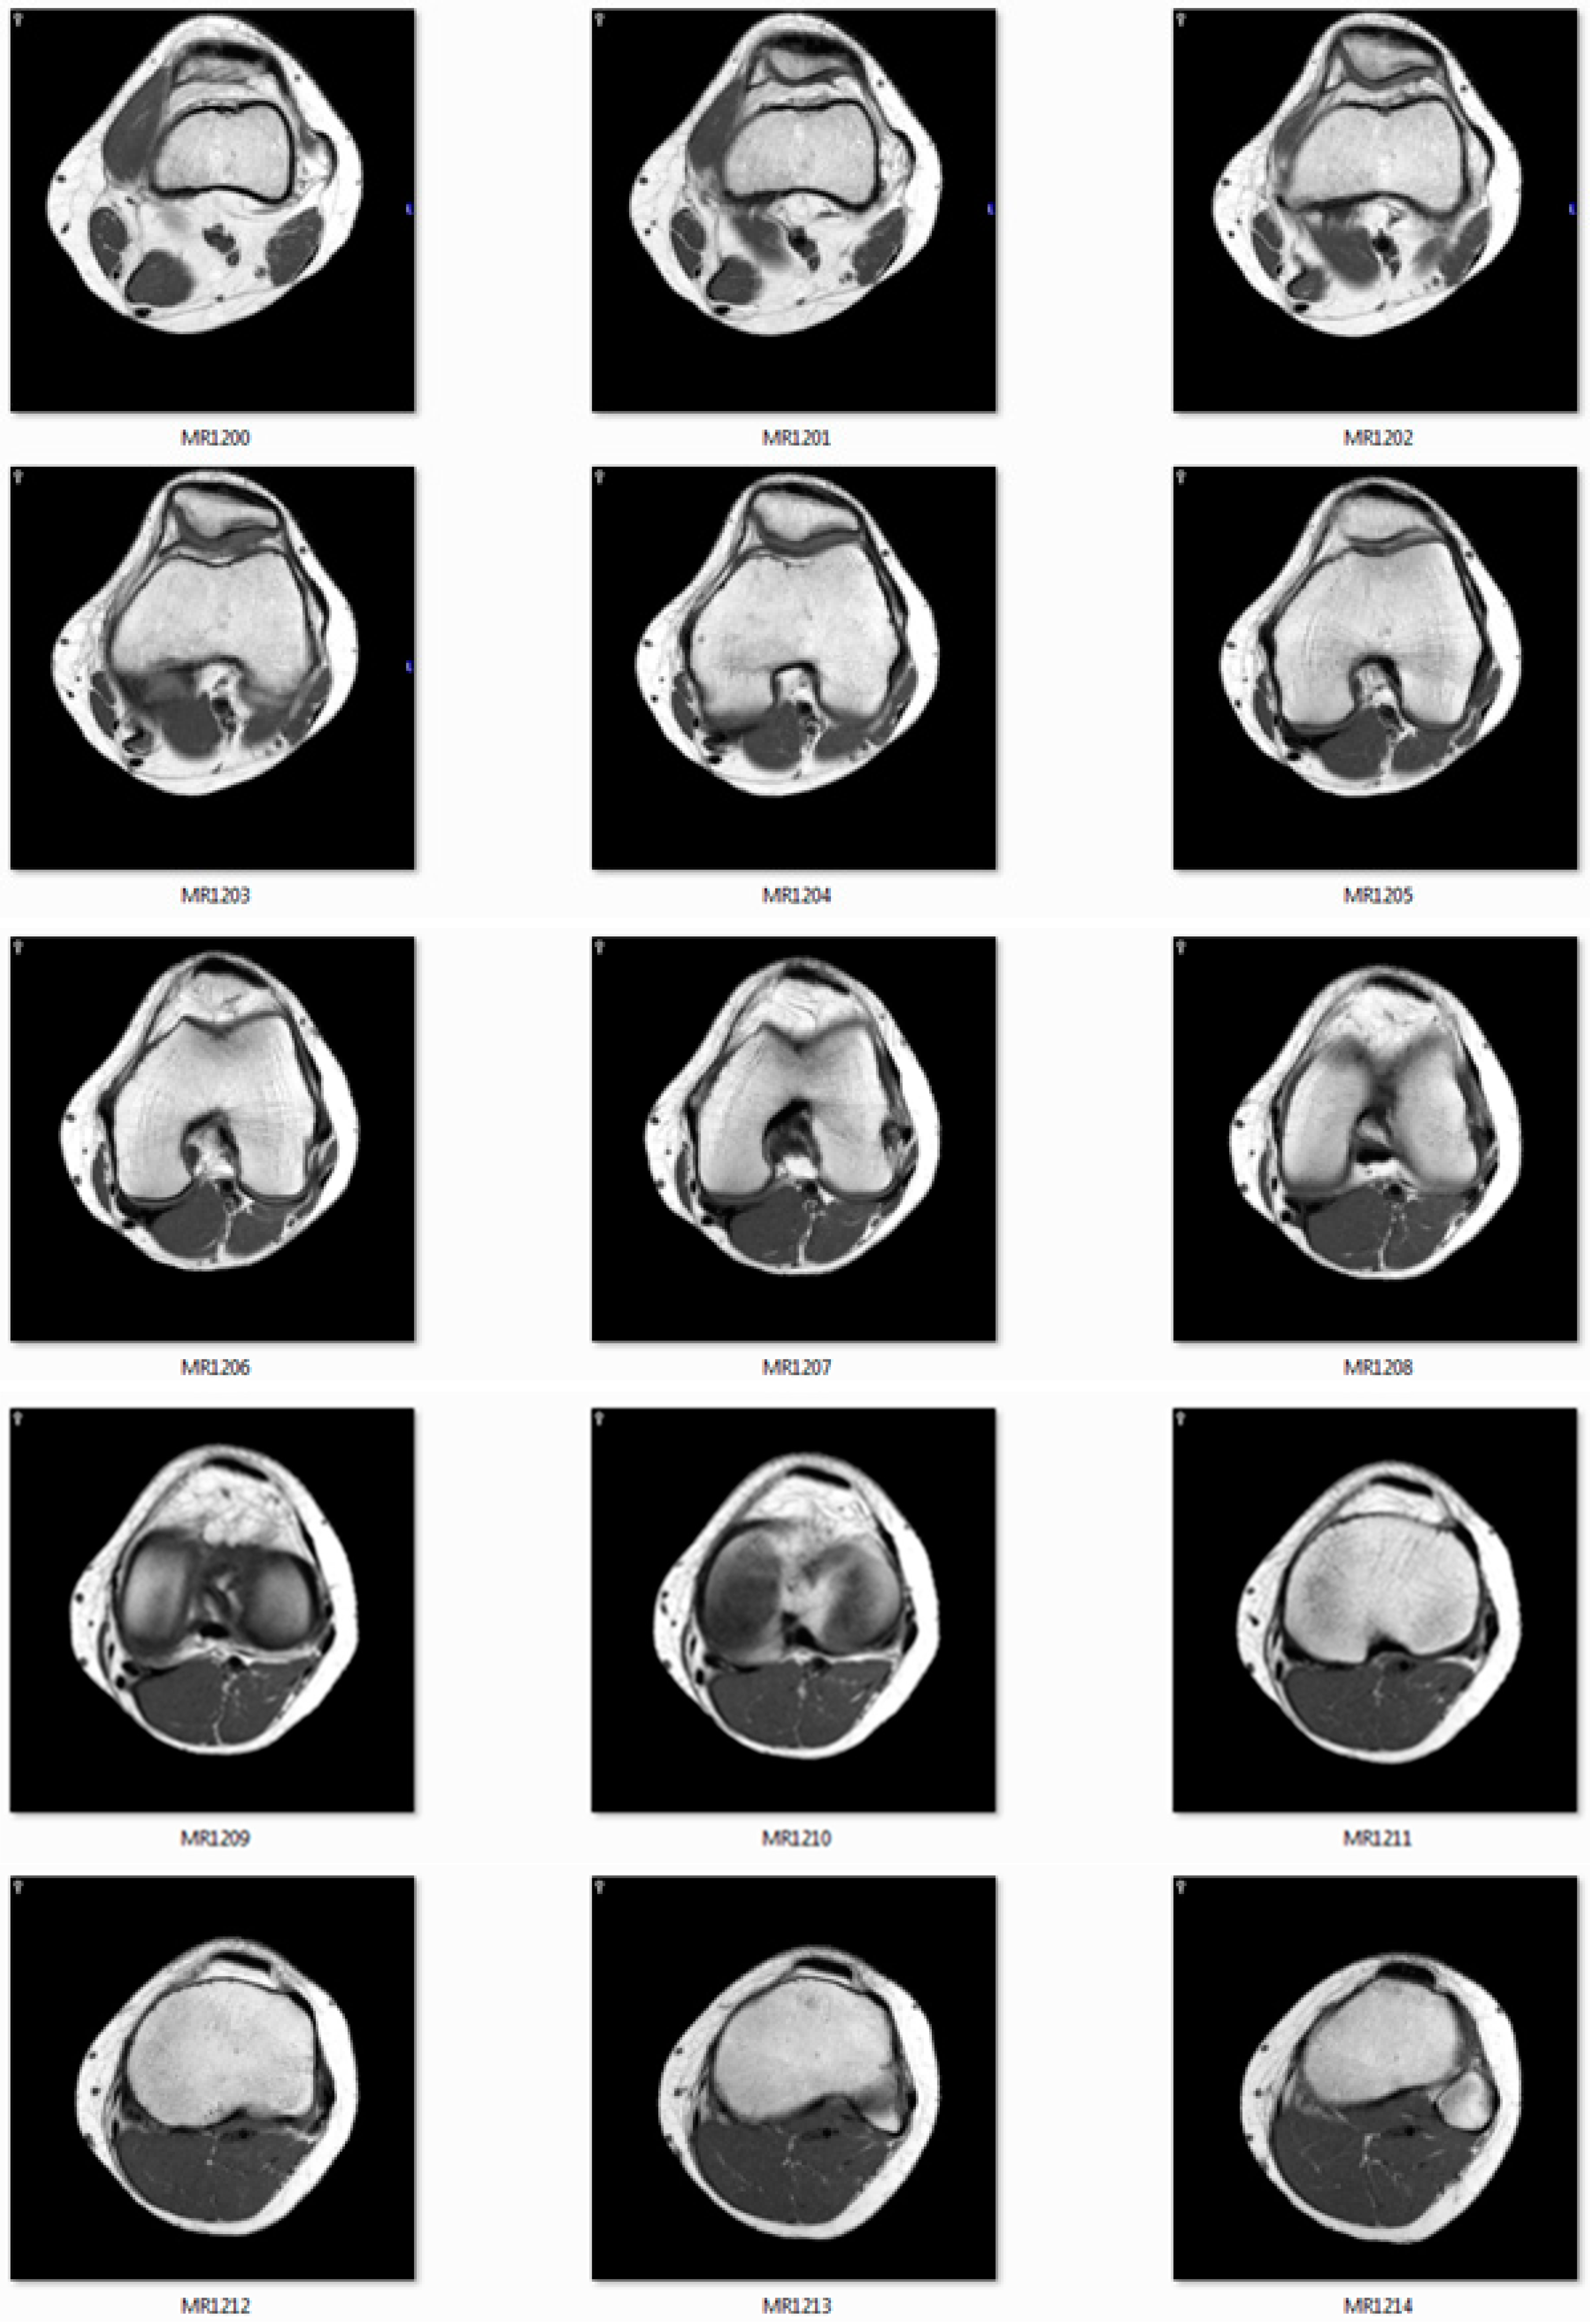

The CT/MRI of 32/64/128 slides must be provided to use as input images. Figure 11 shows the MRI slides of human knee.

Figure 11.

The image slides used as input data.